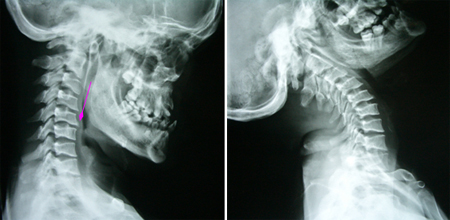

男性,35岁,自幼颅颈、双肩发育异常,双手、上肢肌萎缩3年,加重1月,伴走路不稳。查体:短颈、发髻低、双肩狭小畸形、脊柱侧弯,双上肢及躯干片状感觉障碍,双上肢肌力3-4级,远端更差伴双手爪形,双侧手指伸直困难,双侧病理征阳性。术前影像学资料显示:颅底凹陷、寰枕融合、颈椎生理曲度消失伴退行性改变,小脑扁桃体下疝入椎管伴脊髓空洞(达T8水平)。